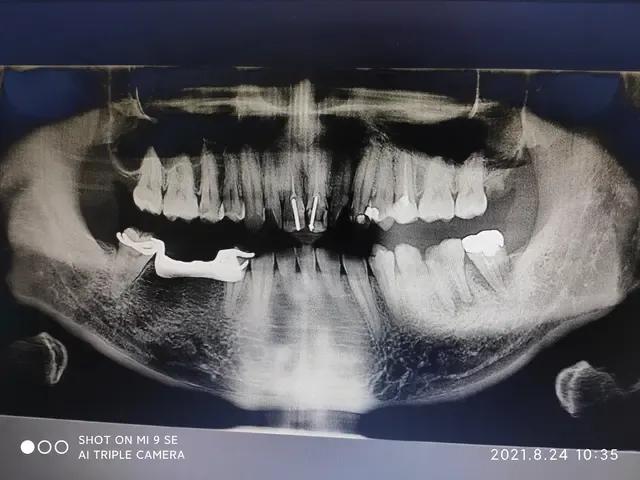

单纯蛀牙不会疼痛,疼痛是蛀到牙神经了,所谓的牙髓炎,需要去专门的口腔医院儿童口腔做根管治疗,以及,补牙。